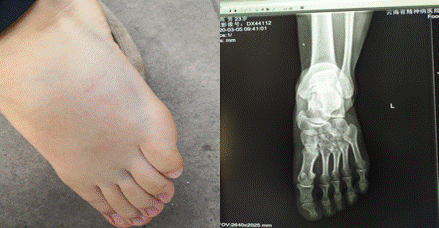

3月3日下午,我院护士刘高在体温监测点上班过程中遭遇大风天气掀翻了帐篷、桌子造成了足背受伤。

为传达院工会对职工的关怀,我院工会主席柳贵明,护理部冒才英主任、马润娟副主任及谭澍带上礼品和工会慰问金前去探望职工刘高。现场了解职工情况,幸在没有造成骨折,只是肌肉、肌腱受到挤压引起肿胀,目前平地走路已不成问题,爬楼过程中足背用不上力。柳贵明主席叮嘱员工保持良好的心态,多注意休息,减少站立时间,争取早日恢复如初。